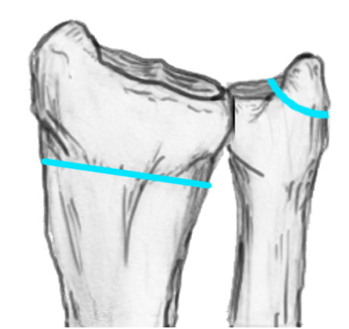

Radial angles

| Volar tilt mean 11° | Radial inclination mean 22° | Radius mean 11 mm longer than ulna |